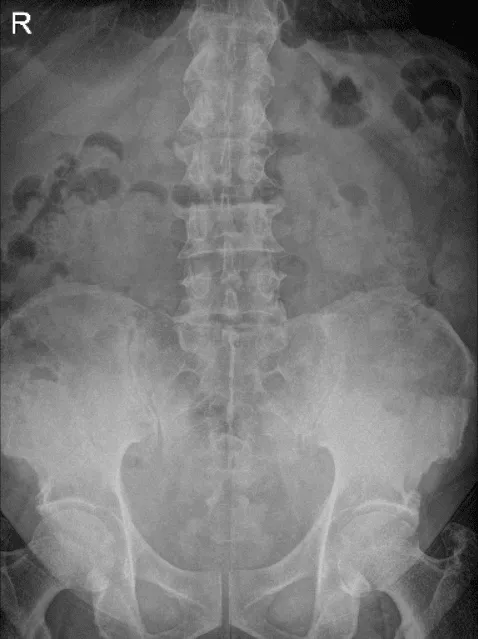

Presentó una radiografía de sus rodillas bilaterales, columna lumbar y mano derecha de Zwanger. Los resultados de sus radiografías mostraron cambios degenerativos osteoartríticos leves. No hay fracturas. Para su columna lumbar, cambios degenerativos lumbares multinivel leves. Para su mano derecha, mano derecha normal.

LS Spine X-ray Flex/Ext sin oblicuos